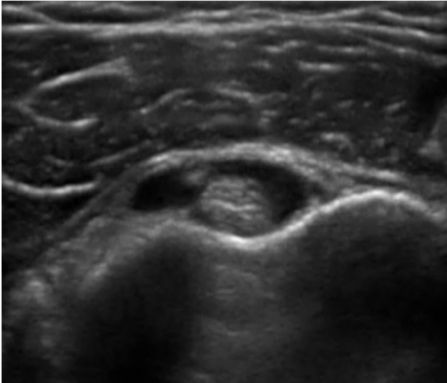

Bicipital tendinitis is a condition caused by inflammation of the long head of the biceps muscle’s tendon. It’s commonly caused by sudden overuse of the muscle and rotator cuff pathology such as muscle or tendon tears, chronic impingement, multidirectional shoulder instability, calcifications, and deconditioning. Signs in physical examination correlating with bicipital tendinitis are pain at the bicipital groove and a positive provocative test such as Speed’s test and Yergason’s test, although studies have shown that their sensitivity might be poor.1